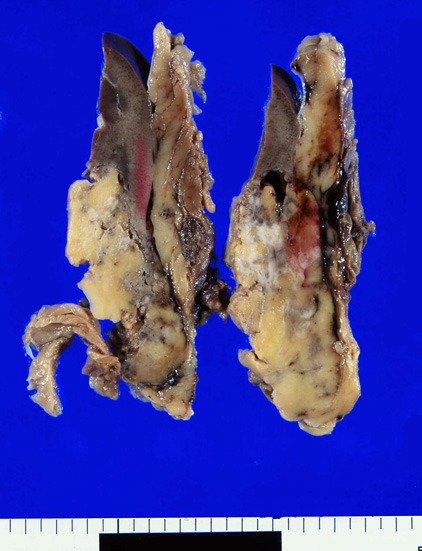

摘出右腎肉眼所見†

クリックすると大きな画像が見られます

- 典型的angiomyolipoma(AMLoma)は腎実質の一部を置換する腎内腫瘍である。病変サイズは大小さまざまで被膜病変は数ミリを越すことはまれな一方, 腎実質腫瘍は最大径が3-20cm(平均9.4cm)となり大型の腫瘤は周囲の構造を圧迫することになる。通常は単発であるが20%の例では多発する。

- 腫瘍はまれに, 腎杯, 腎静脈内に破綻することや腎集合管系, 下大静脈に進展することがある。

- AMLomaは境界のある腫瘍であるが, 被膜はもたず隣接する腎実質を犠牲にして腫大する傾向があるため腎実質は腫瘍に取り囲まれ腫瘍内部に取り残されることになる。 取り込まれた腎尿細管は拡張して嚢胞を形成する。ひどい場合には多嚢胞腎様になりtuberous sclerosis患者さんに多い。

- 通常分葉状で黄色, わずかに油脂状の腫瘤。平滑筋が主要成分の場合は灰白色で硬い。出血はよく起こり症状のある例ではとくにありふれた現象である。腫瘍全域におよぶ出血もありうる。